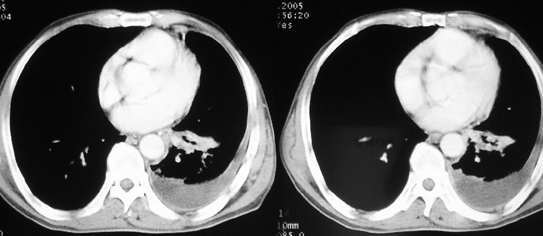

以下是引用jiajie在2005-11-6 22:07:00的发言:[br]1)左肺下叶阻塞性肺炎,胸腔积液,中心型肺癌可能大,建议纤支镜。[br]2)结合30年打石史,双肺弥漫性小结节考虑矽肺。

以下是引用sdqzwyx在2005-11-7 19:59:00的发言:[br]双肺弥漫大小不等的粟粒状结节影;肺纹理走行失去自然,粗细不均,边缘不规则,小叶间隔增厚;左上肺示不规则形致密影,从斑块边缘向周围伸出长短不一的致密索条影,临近的血管、支气管和叶间胸膜等结构受牵拉移位;左下肺示不规则团块状影,其内示空洞,洞内壁尚光整,左侧胸腔积液。右肺下叶背段亦示部分病灶融合。双肺可见局限性肺气肿。[br]诊断:结合病史符合三期矽肺表现(少数矽肺纤维斑块内可以形成空洞,一般认为是斑块中央感染引起坏死所致)但尘肺病人易合并肺结核,诊断可为三期+tb。所以此病人应进一步检查是否合并结核。